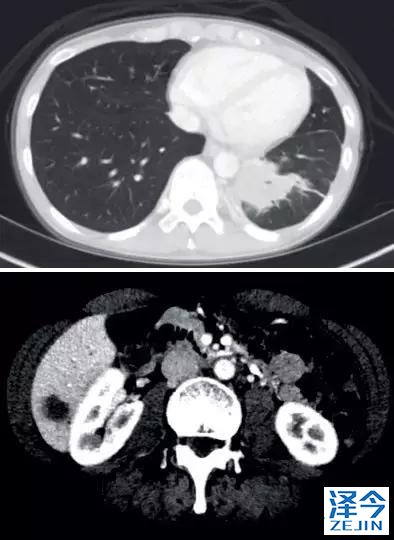

一位77岁的女性患有EPS15-NTRK1 IV期非小细胞肺癌,我们可以看到她的双肺满是病灶,并且出现了肝脏和脑转移,可以说是非常非常晚期了,

肺靶病变达到缓解,我们可以明显的看到前后的图像,病灶明显缩小了,

脑转移病变显示缩小了95%!

初始, 2018年6月 3周期 2018年8月